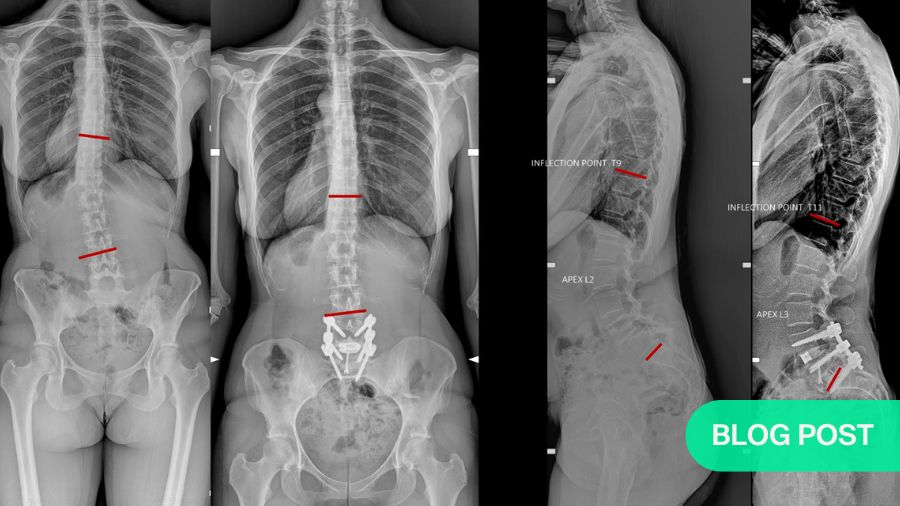

TraumaJune 25, 2025

Cervical Subaxial Facet Injuries: evaluation, management, and how to use the AO Spine Classification System

BY DR RATKO YURAC AND DR ANDREI JOAQUIM